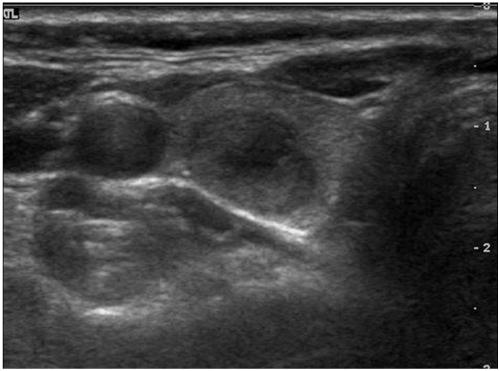

The common US findings for MTCs were solid internal content (91%), an ovoid to round shape (57%), marked hypoechogenicity (52%) and calcifications (52%). Among the 21 cases of MTC nodules, 17 (81%) were classified as suspicious malignant nodules. The mean size (longest diameter) of MTC nodules was 19 +/- 13.9 mm and the mean size (longest diameter) of PTC nodules was 11 +/- 7.4 mm; this difference was statistically significant (p < 0.05). An ovoid to round shape was more prevalent for MTC lesions than for PTC lesions (p < 0.05).

MTC常见的US表现为内部实性成分(91%)、卵圆形至圆形(57%)、明显低回声(52%)和钙化(52%)。在21例MTC结节中,17例(81%)被分类为可疑恶性结节。MTC结节的平均大小(最长直径)为19±13.9mm,PTC结节的平均大小(最长直径)为11±7.4mm;这种差异具有统计学意义(p<0.05)。MTC病变中卵圆形至圆形比PTC病变更常见(p<0.05)。